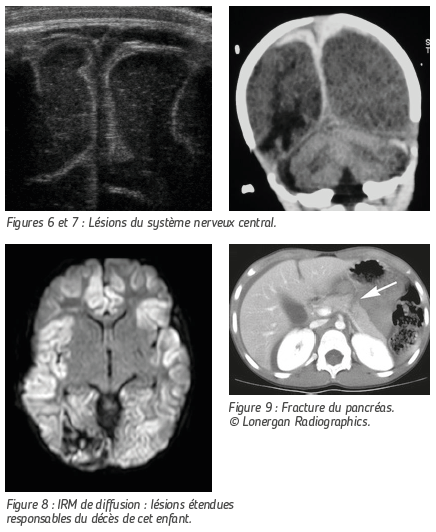

LÉSIONS DU SYSTÈME NERVEUX CENTRAL

Ici encore, le mécanisme lésionnel le plus fréquent chez le nourrisson est le secouage. L’enfant ainsi maltraité peut alors souffrir de graves lésions cérébrales dont les séquelles seront responsables de handicap et qui peuvent entraîner la mort de l’enfant.

L’échographie transfontanellaire n’est pas formellement indiquée mais dans certaines circonstances, elle permet de mettre en évidence fortuitement et de façon non irradiante les lésions hémorragiques interhémisphériques « biphasiques » typiques.

Le CT Scanner est d’accès facile et permettra lui aussi de mettre en évidence les zones de contusion, les hématomes et les ruptures des « veines ponts ».

L’IRM est indispensable pour le bilan lésionnel complet. Cet examen n’est pas pratiqué en urgence car il nécessite une anesthésie générale chez le petit enfant.

Les séquences adaptées permettent d’évaluer l’étendue des lésions anoxo-ischémiques dont le pronostic peut être très sombre en matière de séquelles, voire de survie de l’enfant.

L’enfant maltraité peut être aussi victime de lésions viscérales : fracture du pancréas, du foie ou de la rate. L’échographie et le scanner permettent d’en faire le diagnostic.